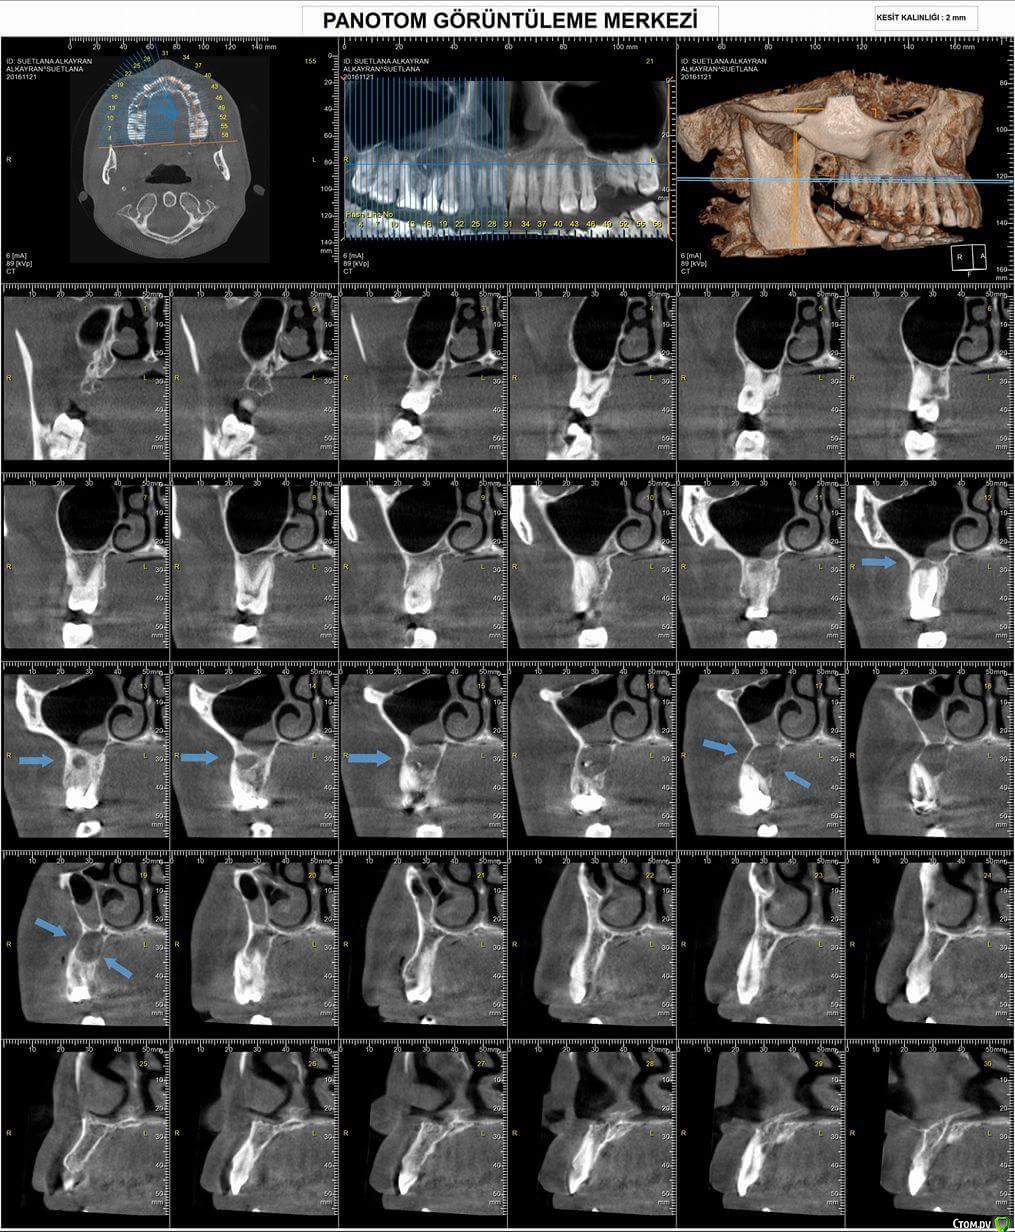

Sweetlana Опубликовано 14 января, 2017 Поделиться Опубликовано 14 января, 2017 В последнее время многие клиники предлагают услугу удаления зубов ультразвуком (аппарат пьезотом, например). Судя по видео, процедура действительно проходит намного проще, чем при традиционном удалении и зуб сам выпадает из лунки. Кто практикует подобное? Есть ли те, кому удаляли ультразвуком? Отзывов найти не могу.Нужно удалить два коренных зуба на верхней челюсти из-за большой кисты (5 и 6 зубы). Понимаю, что с локальной анестезией больно не будет, но до паники боюсь раскачивания зуба в разные стороны и последующего хруста при удалении! Действительно ли применение ультразвука позволяет избежать этих неприятных ощущений? Ссылка на комментарий